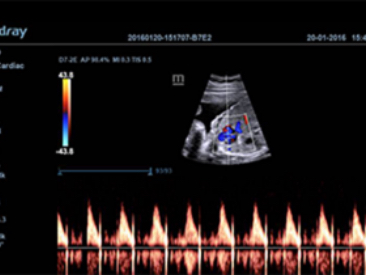

Obrazy kliniczne